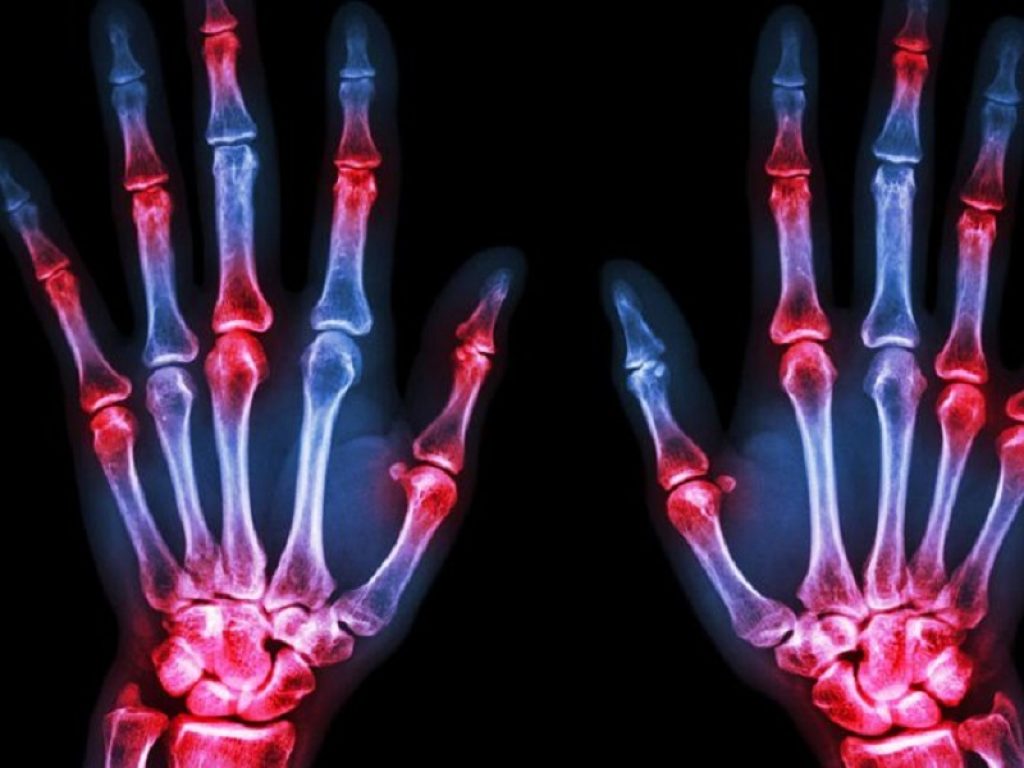

La gestione moderna dell’artrite reumatoide (AR) dovrebbe basarsi sul ricorso a strategie di trattamento mirate che puntino al raggiungimento della remissione o di una ridotta attività di malattia in ogni paziente, ricordano i ricercatori nell’introduzione allo studio. Tuttavia non è infrequente osservare la progressione del danno strutturale articolare nonostante i pazienti soddisfino i criteri di remissione raccomandati, associata ad una compromissione funzionale e ad una ridotta qualità della vita.

L’infiammazione valutata alla risonanza magnetica, in particolare l’osteite, si è dimostrata un forte fattore predittivo della successiva progressione del danno osseo nei pazienti con AR attiva e in quelli in remissione.